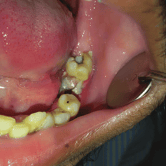

Extracción de Muelas del Juicio

La extracción de las muelas del juicio es un procedimiento quirúrgico para remover los terceros molares que pueden causar dolor, infección o daño a otros dientes debido a su posición o crecimiento anómalo.

Los pacientes pueden experimentar dolor, hinchazón y, en algunos casos, infección alrededor de estas muelas.

El tratamiento incluye la extracción quirúrgica para prevenir o resolver complicaciones.